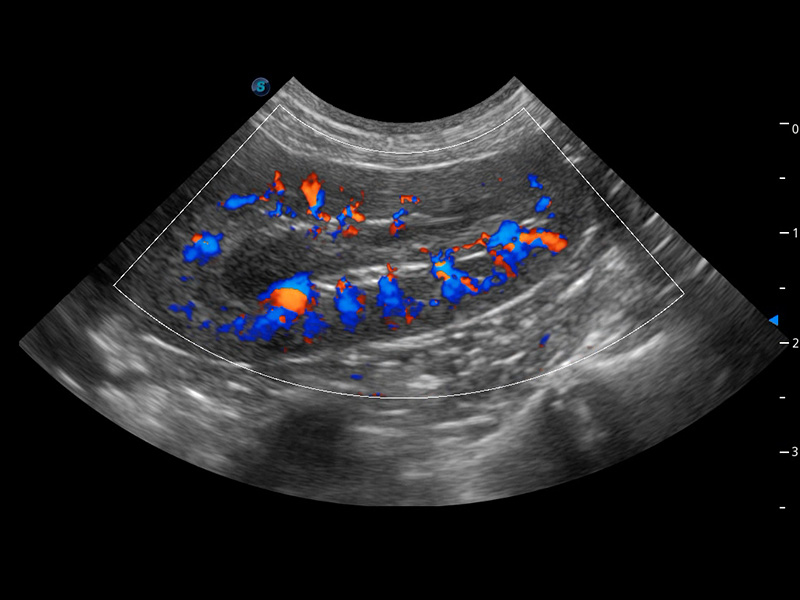

ProPet 60 作为一款高端台式动物超声设备,为动物医生的日常诊断提供了一系列贴合动物临床需求、解决临床实际问题的高级成像功能。凭借全系列高清探头,满足医生对腹部、心脏、生殖、浅表、肌骨等成像的所有需求,切实帮助您提升检查效率,提高诊断信心。

动物是人类最亲密的朋友和最值得信赖的伙伴。1xBET也一直致力于探索动物专用的超声影像解决方案。 全新推出的ProPet系列,是1xBET在动物超声影像智能化、专业化、精准化的一次跨越式革新。动物不能用言语来表述自己的不适,通过超声影像,ProPet系列搭建了动物医生与不同物种沟通的“桥梁”,为动物医生注入了“治愈之力”。